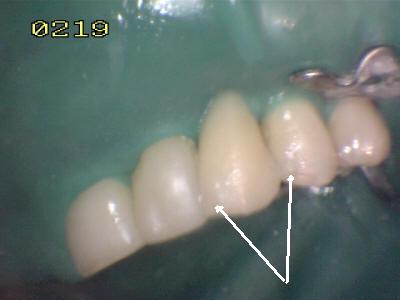

• Chequear la oclusión en céntrica y excéntrica con papel de articular los contactos céntricos deben ser puntiformes. Y en excéntrica no debe haber contacto si existen los mecanismos de la desoclusión.